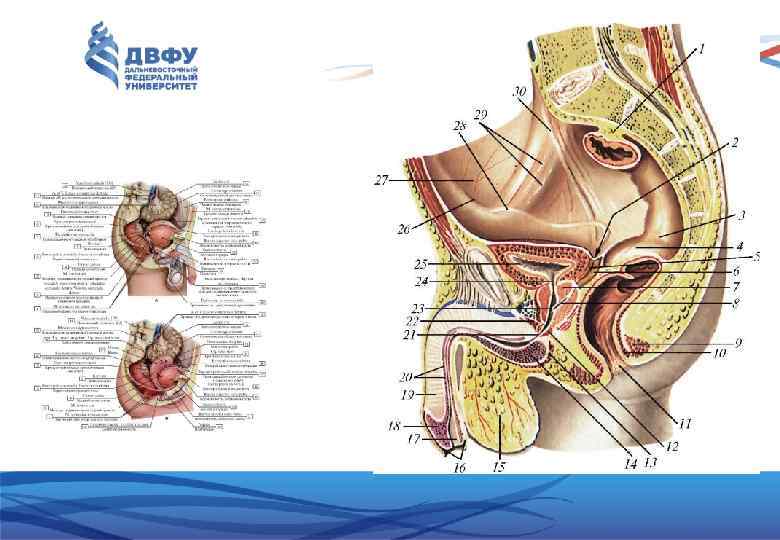

Анатомия малого таза: детальные схемы и изображения